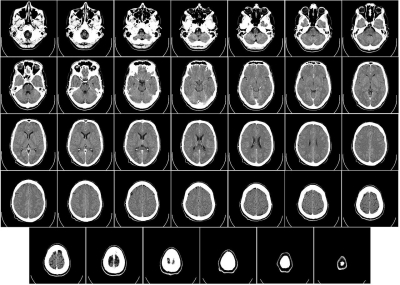

우리나라에서 단일 질환으로 사망률 1위는 뇌졸중이라고 하는데요. 뇌졸중은 뇌의 혈관이 좁아지면서 혈관이 막히며 발생하는 질환입니다.

뇌졸중은 초기에 치료하면 그만큼 예후도 좋습니다. 뇌졸중 전조증상에 대해 알아보고 미리 건강을 챙기면 좋을 것 같습니다.

뇌졸중 전조증상